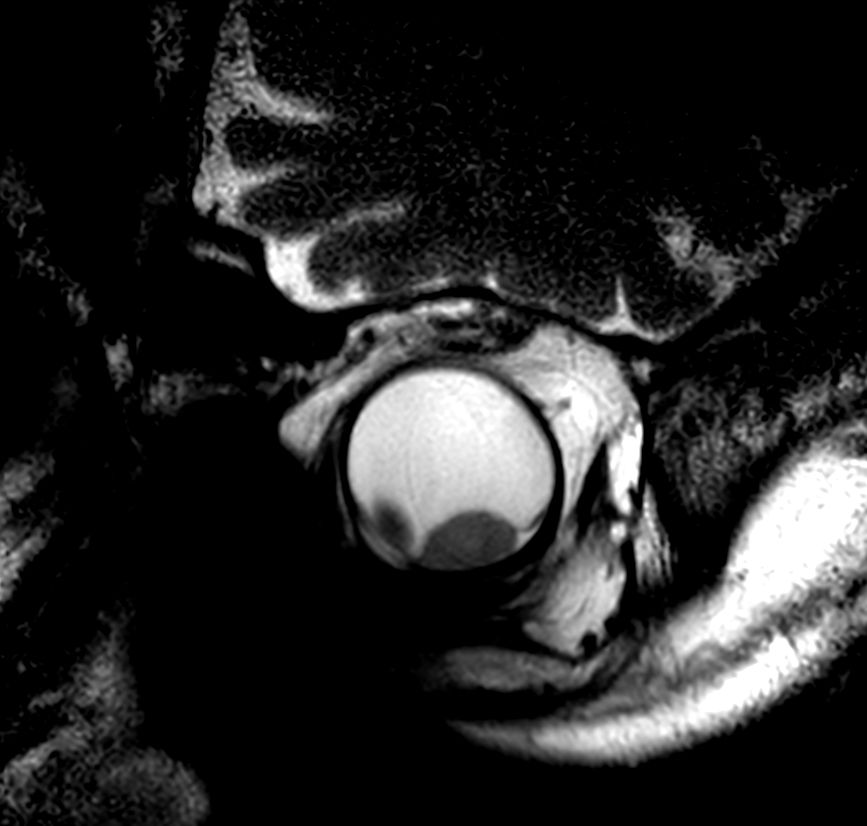

4 different 3D isotropic sequences, T1W with and without fat saturation, T2W and T1W fat saturation post-contrast are used to evaluate the tumor prior to treatment. Isotropic sequences are used to allow for good quality multiplanar reconstruction corresponding to the location of the tumor; as the tumor can be located anywhere in the eye, optimal visualization often requires an assessment of different oblique planes, which is facilitated by the 3D isotropic sequences. The pre-contrast sequences help evaluate the tumor size and location and the post-contrast sequence provides additional information such as identifying tumor that has seeped through the sclera behind the eye and differentiating tumor vs associated retinal detachment.